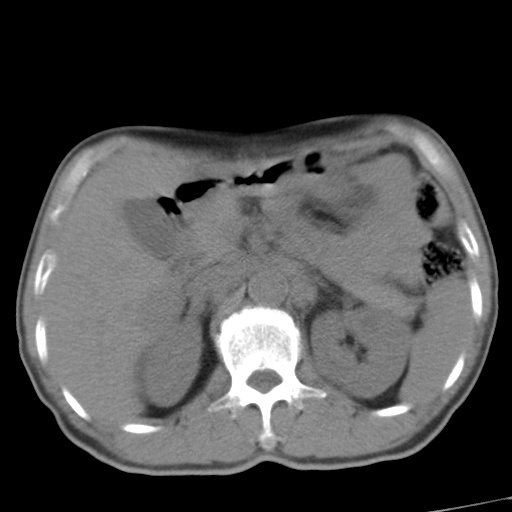

标题: CT17975:请求会诊。男、57岁。上腹部胀痛2天。临床诊断:糜 [打印本页]

标题: CT17975:请求会诊。男、57岁。上腹部胀痛2天。临床诊断:糜

考虑胃癌并肝脏及腹膜后淋巴结转移;不排除淋巴瘤。

肝内转移瘤,腹腔及腹膜后淋巴结转移。